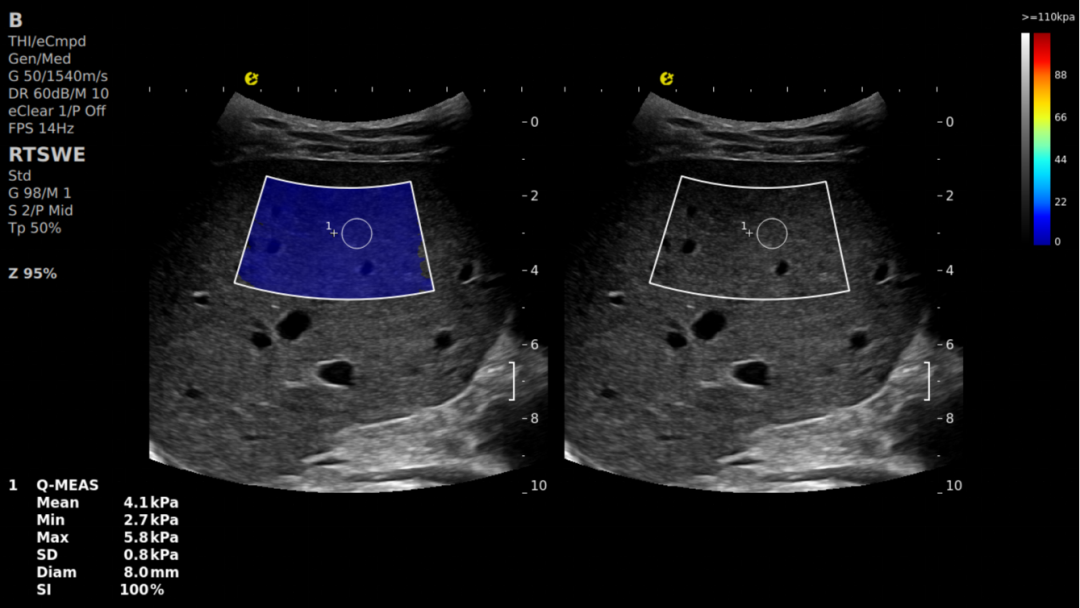

E成像-RTSWE®

通过精准量化肝脏硬度,为肝纤维化分期提供客观的kPa值依据(参考Baveno VII共识对肝脏硬度检测的相关标准),其鉴别F2期及以上纤维化的AUROC值达0.87,显著优于传统血清学指标(如FIB-4、APRI),相关数据来自多中心临床验证研究。